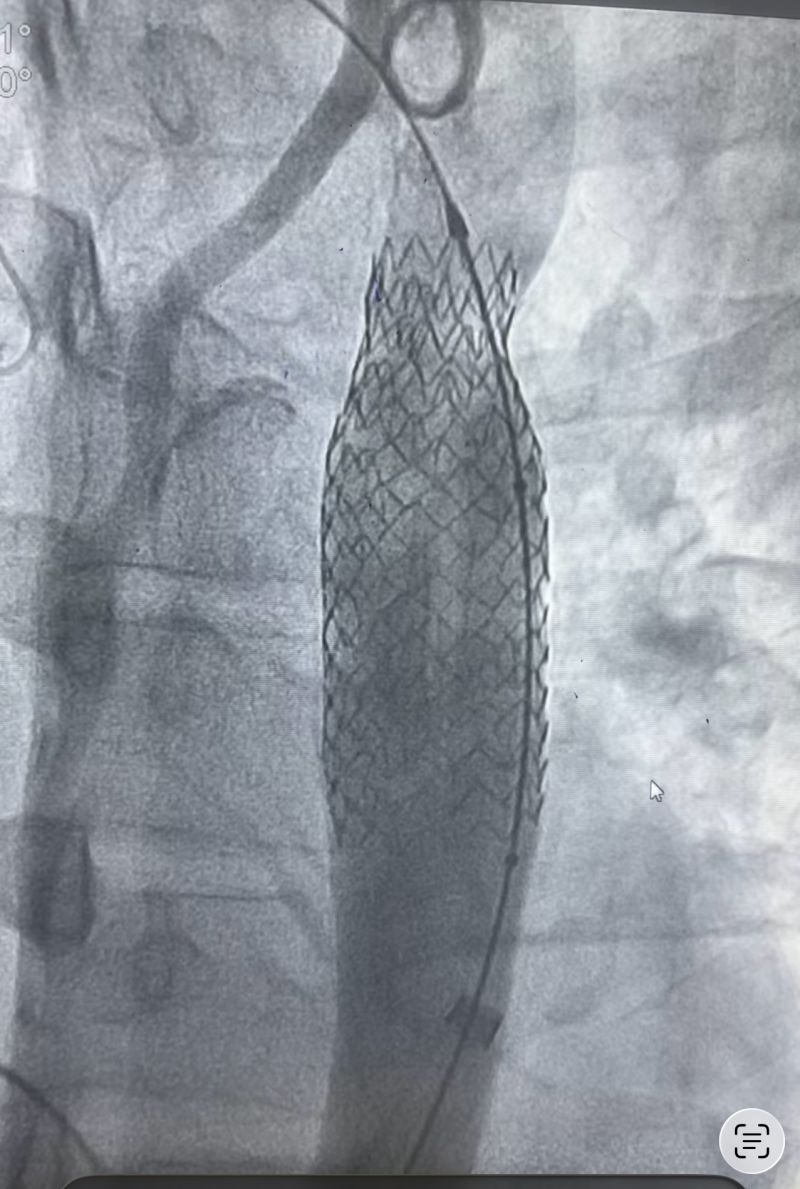

The procedure involved deployment of a Zephyr CS stent graft (18 ร 69 mm), followed by post-dilation using a 24 ร 60 mm Andromed balloon.

The final outcome was excellent, with complete resolution of the translesional gradient.